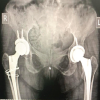

X-ray right pelvis showing no lesser trochanter, greater trochanter tilted upward and laterally, absence of lateral cortex of femur, prosthetic tip was migrated medially, and the acetabular surface was eroded (Fig. 1). In addition, bone mineral density (BMD) measurements revealed spine BMD of −3.9 and femur BMD of −4.3, indicating osteoporosis.

Stage one: After maintaining all aseptic precautions, we employed a lateral approach. The greater trochanter was identified with prosthesis. Greater trochanter was severely osteoporotic. There was a chance of fracture while removal of the implant. Dislocation of head of prosthesis and removal of it were done successfully (Fig. 2). Acetabular surface was deficit near 30%. Removal of surrounding tissues was done carefully. After that, we kept an antibiotic-mixed cement as a spacer (Fig. 3) and gave vancomycin powder within the acetabular cavity. After closure, we planned to perform the 2nd stage of surgery 4 weeks later. Stage two: Due to the unavailability of the implant, we had done 2nd stage of surgery 10 weeks (2.5 months) later. We used the same lateral approach with extension up to mid-thigh and removed the cement spacer. We reamed the acetabulum very carefully and found the bone very soft and fragile. For this reason, a non-cemented cup was inserted (Fig. 4) and fixed with three screws. Shaft of the femur was exposed properly and found absence/deficient of the lateral cortex of it. Prosthetic end of medullary cavity was found blocked by bone. Initially, we tried to reaming the medullary cavity under fluoroscopy guided by 7 mm reamer. It was very difficult to achieve the reaming portion at the blocked area. Introduction of stem was difficult due to the chance of re-fracture and there was a big gap, measuring 8 cm × 1.25 cm at the lateral cortex of the femur. To cover this gap, the mid-third of the fibula (harvested by fibulectomy) (Fig. 5) was used as a bone graft, which was then grafted and fixed using surgical wiring (Fig. 6). Afterward, we faced difficulty during cementing technique. During introduction of cement into the femoral medullary cavity, cement was found leaked from the space of the grafted bone. Then leakage was carefully protected. Femoral stem was introduced carefully so that it was be in a position to medullary cavity (Fig. 7). A drain tube was kept in situ, then with aseptic precautions, we closed the surface.